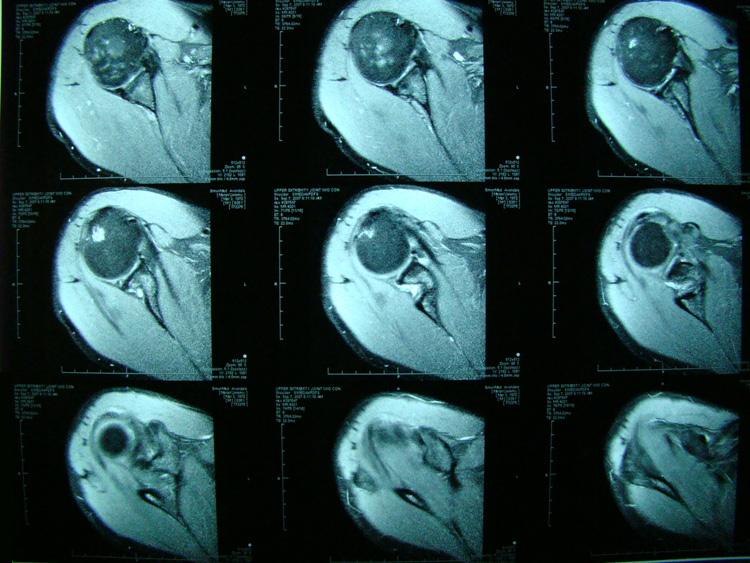

This patient presented with shoulder pain that interfered with work and exercise. The visible fluid-filled cysts on the “Before" MRIs are from chronically injured rotator cuff tendon roots.

The patient underwent treatments of a highly specialized fine-needling technique pioneered by Dr. Tallman.The follow-up MRI was done 2 months after his 6th treatment. He was released with a pain-free, full range of motion with unrestricted activities.